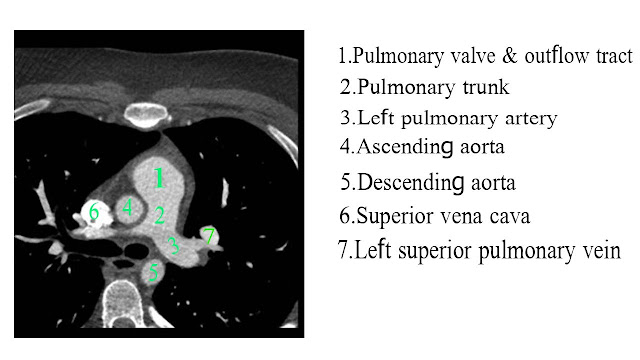

CT scan of heart

_Heart

__axial